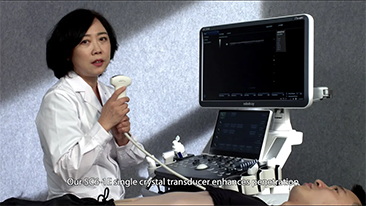

Las soluciones de imĂĄgenes generales de Resona de Mindray ayudan al personal clĂnico a realizar diagnĂłsticos y obtener resultados de tratamiento mĂĄs precisos y eficientes a travĂ©s de sondas para aplicaciones de subdivisiĂłn integrales y herramientas de aplicaciĂłn clĂnica eficientes.

Productos generales de generaciĂłn de imĂĄgenes